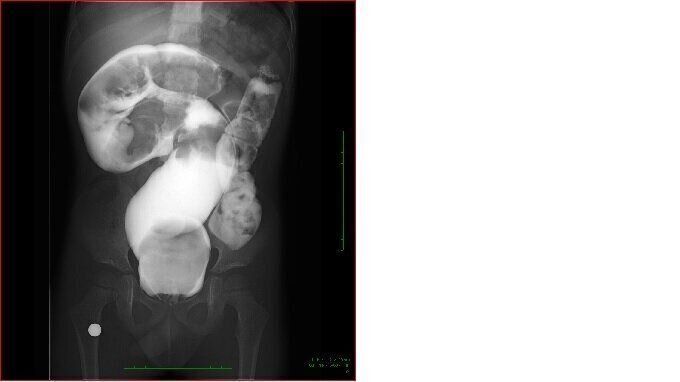

小児慢性機能性便秘症と診断された子どもの腸の写真(4才0カ月)白い造影剤で浮き上がった黒い部分が、腸にたまった便。肛門(こうもん)の上に大きいかたまりが見えます。